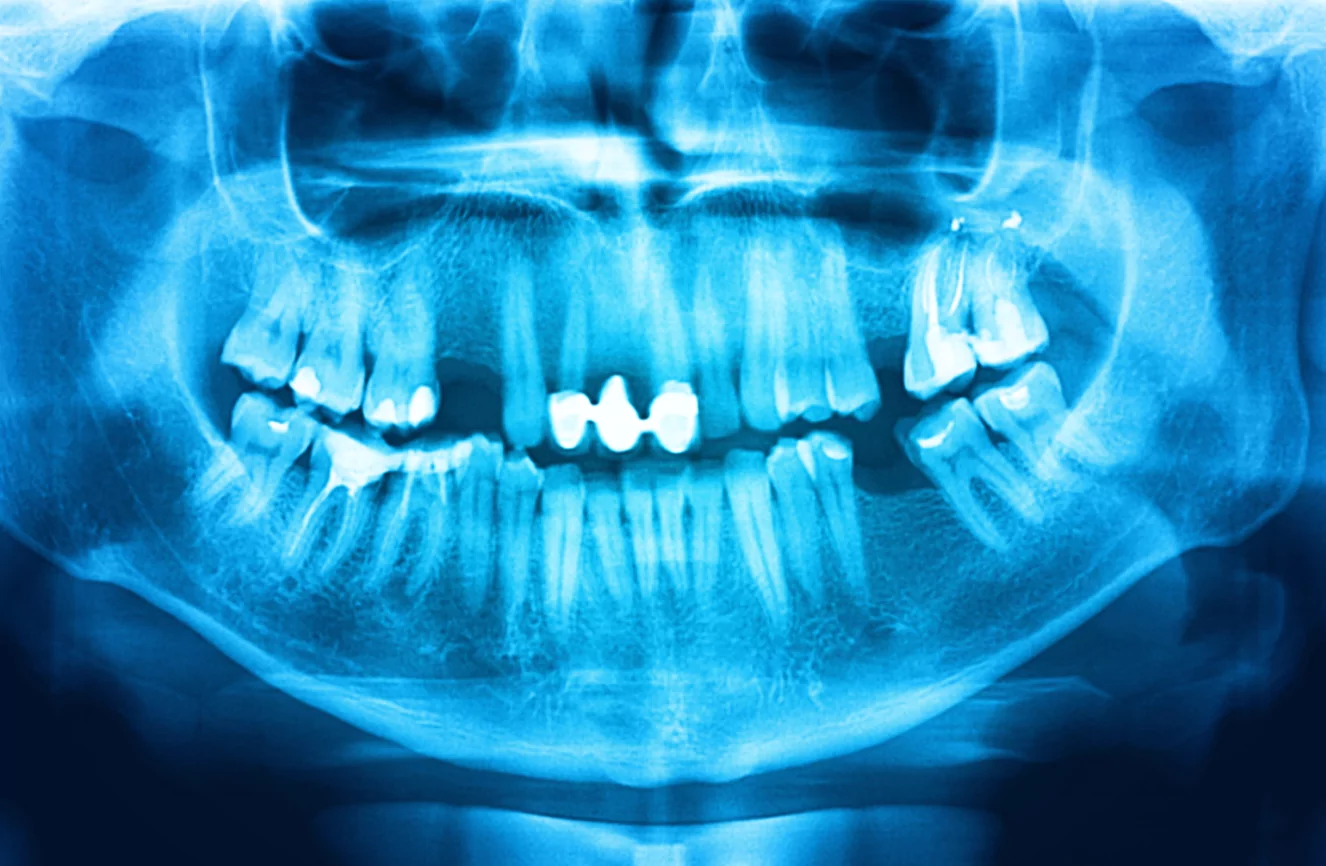

Digital X-Rays

Traditional dental X-rays have been “good enough,” but digital X-rays provide clearer and a much more accurate picture of what’s going on inside a patient’s mouth. This makes it easier for the doctor to diagnose issues. Leaks or breaks in fillings that used to go unnoticed, often leading to root canals, can now be found and treated before major damage is done. We can also view your entire mouth in one shot, including the upper and lower jaws, with panoramic digital images.